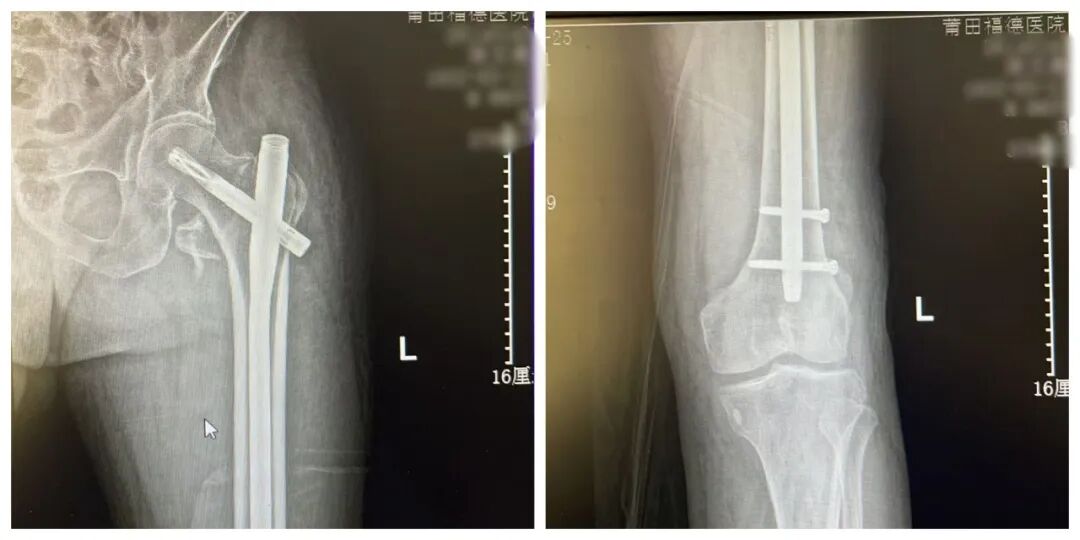

尽管 患者高龄 给手术带来了不小压力,但骨科手术团队凭借精湛医术和丰富经验,顺利完成了手术。术后复查DR,提示 金属内固定在位,断端对位良好。

患者术后影像

手术过程顺利,术后 复查DR ,显示 断端对位良好,金属内固定在位, 手术效果满意。